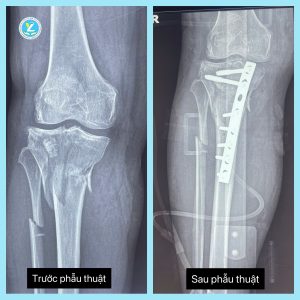

Tại đây, người bệnh đã nhanh chóng được các bác sĩ thăm khám, chẩn đoán và đi đến kết luận: Gãy xương chày Schatzker loại VI chân phải ( là loại gãy mâm chày nghiêm trọng nhất, đặc trưng bởi gãy cả hai mâm chày (trong và ngoài) kèm theo gãy rời khỏi thân xương). Kết quả siêu âm cho thấy hình ảnh tràn dịch, tràn máu trong ổ khớp gối phải.

Tiếp nhận trường hợp này, BS CKI. Hoàng Mạnh Thuần – Trưởng khoa Ngoại TH – CK, TTYT khu vực Yên Lập cho biết: “Đây là một trong những ca phẫu thuật chuyên khoa lớn tại Trung tâm. Người bệnh bị gãy phức tạp xương chày, do tính chất gãy phức tạp, gãy không vững do nhiều mảnh xương vụn nên phương án phẫu thuật là thực hiện kết hợp xương gãy bằng nẹp vít, tiếp đến là phải mở dẫn lưu khớp để giải phóng khớp. Đây là phương tiện kết hợp xương theo công nghệ mới và phù hợp cho loại gãy này”

Sau khi thăm khám và làm các xét nghiệm cần thiết, trưởng kip mổ do BS CKI. Hoàng Mạnh Thuần – Trưởng khoa Ngoại TH – CK thực hiện. Sau 2 giờ ca phẫu thuật diễn ra thành công, các vị trí đặt nẹp vít đều đúng dự kiến. Kết quả X-quang sau phẫu thuật: Hình ảnh xương thẳng trục, mảnh xương vỡ đúng vị trí. Đây là một ca phẫu thuật khó, vì xương gãy thành nhiều mảnh nhỏ, phức tạp. Thời gian phẫu thuật kéo dài. Hiện tại, người bệnh tiếp tục được chăm sóc và điều trị tại khoa. Dự kiến sẽ được xuất viện trong vài ngày tới.